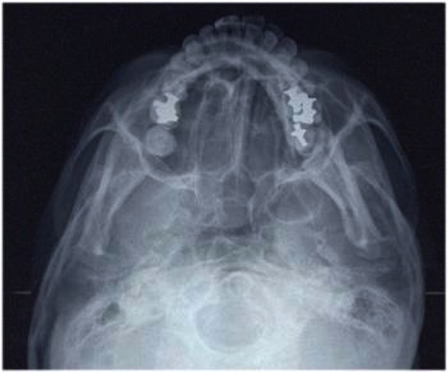

レントゲン写真(上)

レントゲン写真(口全体)